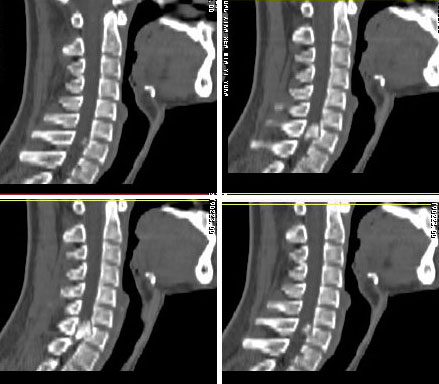

男24岁因一年来感头昏,查体四肢肌力及感觉无异常。颈椎dr未见异常,mri发现c7水平段椎管内左侧占位。患者于7年前有车祸伤病史(但是未检查,自述无异常)。请讨论是否是机化血肿或骨折片,能除外是肿瘤?

强化

椎管内骨性肿块,与第7颈椎左下关节突关系密切,向椎管内生长,第7颈椎椎体左后缘受压变形,边缘可见硬化边,与肿块间间隙清晰。mri扫描肿块内可见骨髓信号,考虑骨软骨瘤可能性大。